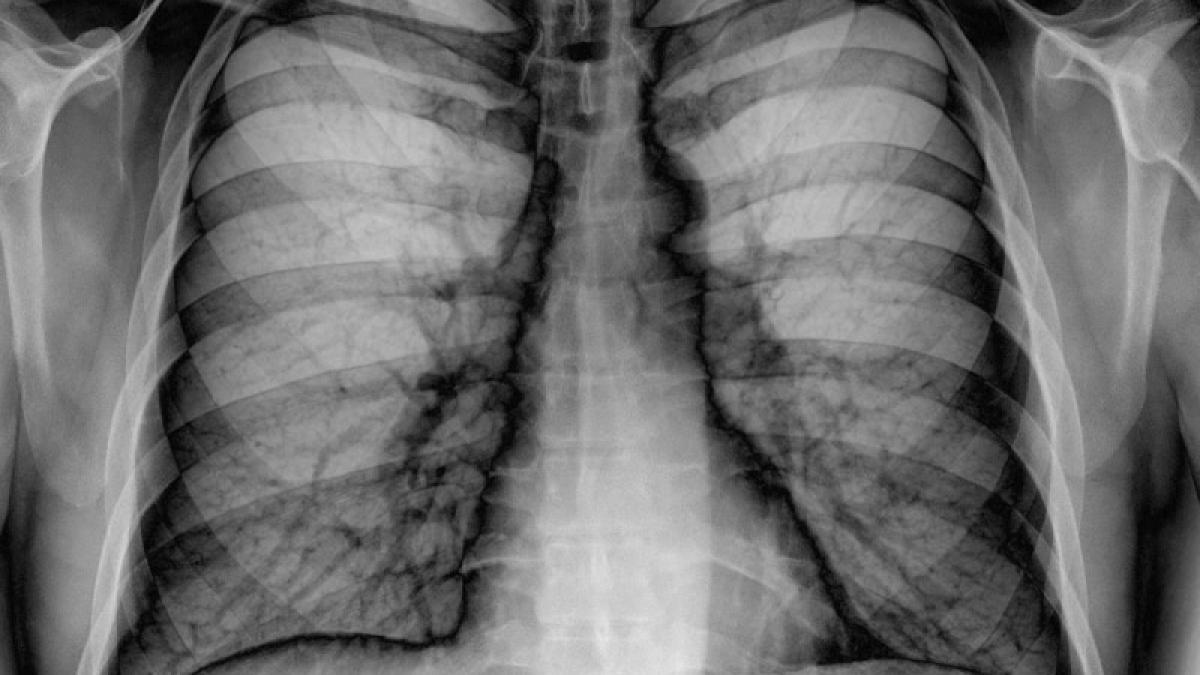

Imaginile care vor convinge FUMĂTORII să renunţe la ţigări. Aşa arată PLĂMÂNII unui bărbat care a fumat 15 ani28 Ian